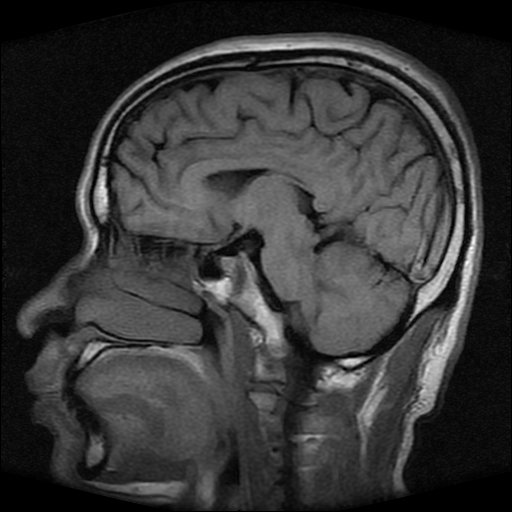

标题: MRI2584:静脉窦血栓?请会诊!

男性,39岁。头晕,视物模糊2月余。血压142/85。矢状窦内高信号有问题吗?

正常脂肪信号影。

正常,若不放心,可以mrv证实

这种病例以前也见过, 但平常的阅片过程比较少注意,而且一些资料上介绍或者图片也比较少,我觉得此病例应该考虑静脉窦血栓。

起码近来我注意的正常人静脉窦内部不是如此信号。

t1wi像可以出现缓慢流速血管呈高信号,应加t2wi及mrv